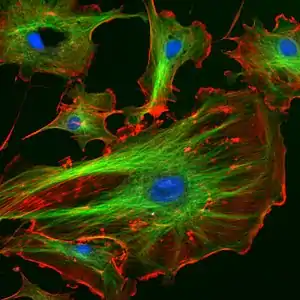

DAPI (pronounced 'DAPPY', /ˈdæpiː/), or 4′,6-diamidino-2-phenylindole, is a fluorescent stain that binds strongly to adenine–thymine-rich regions in DNA. It is used extensively in fluorescence microscopy. As DAPI can pass through an intact cell membrane, it can be used to stain both live and fixed cells, though it passes through the membrane less efficiently in live cells and therefore provides a marker for membrane viability.

Strong fluorescence when bound to DNA led to the rapid adoption of DAPI for fluorescent staining of DNA for fluorescence microscopy. Its use for detecting DNA in plant, metazoa and bacteria cells and virus particles was demonstrated in the late 1970s, and quantitative staining of DNA inside cells was demonstrated in 1977. Use of DAPI as a DNA stain for flow cytometry was also demonstrated around this time.[1]

When bound to double-stranded DNA, DAPI has an absorption maximum at a wavelength of 358 nm (ultraviolet) and its emission maximum is at 461 nm (blue). Therefore, for fluorescence microscopy, DAPI is excited with ultraviolet light and is detected through a blue/cyan filter. The emission peak is fairly broad.[2] DAPI will also bind to RNA, though it is not as strongly fluorescent. Its emission shifts to around 500 nm when bound to RNA.[3][4]

DAPI's blue emission is convenient for microscopists who wish to use multiple fluorescent stains in a single sample. There is some fluorescence overlap between DAPI and green-fluorescent molecules like fluorescein and green fluorescent protein (GFP) but the effect of this is small. Use of spectral unmixing can account for this effect if extremely precise image analysis is required.

Outside of analytical fluorescence light microscopy DAPI is also popular for labeling of cell cultures to detect the DNA of contaminating Mycoplasma or virus. The labelled Mycoplasma or virus particles in the growth medium fluoresce once stained by DAPI making them easy to detect.[5]